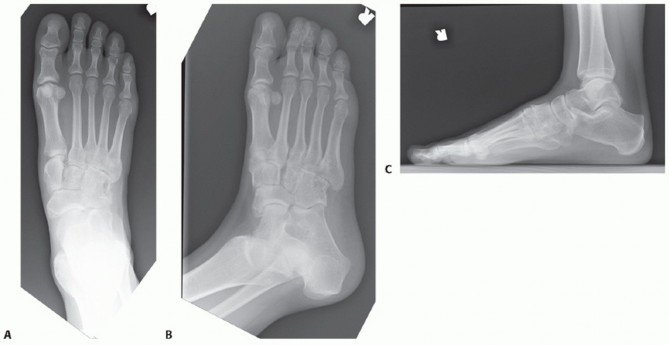

DEFINITION Hallux valgus is a deformity of the forefoot characterized by progressive lateral subluxation of t…

DEFINITION Hallux valgus is a common condition that can affect both adults and adolescents.2,7 Patients compl…